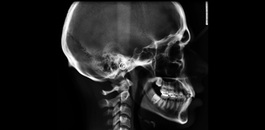

Documentação ortodôntica digital

Documentação composta de radiografias, fotografias, modelos e análises cefalométricas com o objetivo de realizar um estudo detalhada da interrelação das estruturas dento faciais do paciente. Possibilitando a escolha do tratamento correto para o mesmo. Indicação: Tratamentos Ortodônticos e Ortopédicos.

Teleradiografia lateral de perfil

Indicada para realização de análises cefalométricas. Sendo possível a avaliação das estruturas ósseas e respectivas interrelações. Muito indicada para planejamentos ortodônticos e ortopédicos.